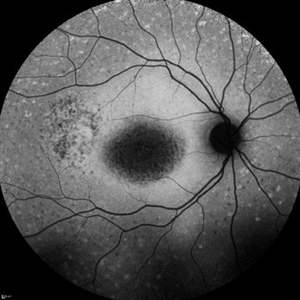

Stargardt Disease

Dec 9 2021 by Filip Kecer

Fundus autofluorescence of a 14-year-old girl with genetically confirmed Stargardt disease.

Photographer: Filip Kecer

Imaging device: Spectralis, Heidelberg Engineering

Condition/keywords: autofluorescence imaging, Stargardt disease